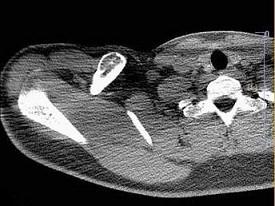

问题 男,18岁,右锁骨轻微疼痛,伴局部肿胀,结合图像,最可能的诊断是?(?)

选项 A.右锁骨正常 B.右锁骨嗜酸性肉芽肿 C.右锁骨骨囊肿 D.右锁骨骨结核 E.右锁骨骨巨细胞瘤

答案 B